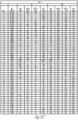

- FIGS. 26A-26R illustrate a table of individual sample cell and culture data of FIGS. 25A-25H , listed in sample order, S/CO and MID immunoassay interpretation, ⁇ -defensin >1 is positive, C-reactive protein (CRP) >3 is positive, total nucleated cells (TNC >3000 is positive).

- Organism organism identified through culture at a maximum of 7 days; most samples (>95%) culture positive within 2 days

- FIGS. 27A-27H illustrate a series of tables of individual sample cells and culture data for samples testing positive for various microorganisms according to an example of the MID immunoassay.

- FIG. 27A is a table of synovial fluid samples testing culture positive for Streptococcus agalactiae or Pseudomonas aeruginosa.

- FIG. 27B is a table of synovial fluid samples testing positive for Staphylococcus lugdunensis.

- FIG. 27C-27D is a table of synovial fluid samples testing culture positive for Staphylococcus aureus.

- FIG. 27E-27F is a table of synovial fluid samples testing culture positive Staphylococcus epidermidis FIG.

- FIG. 27G is a table of synovial fluid samples testing culture positive for Enterococcus faecalis.

- FIG. 27H is a table of synovial fluid samples testing culture positive for Candida albicans, candidaparapsilosis, Candida glabrata, or Candida tropicalis.